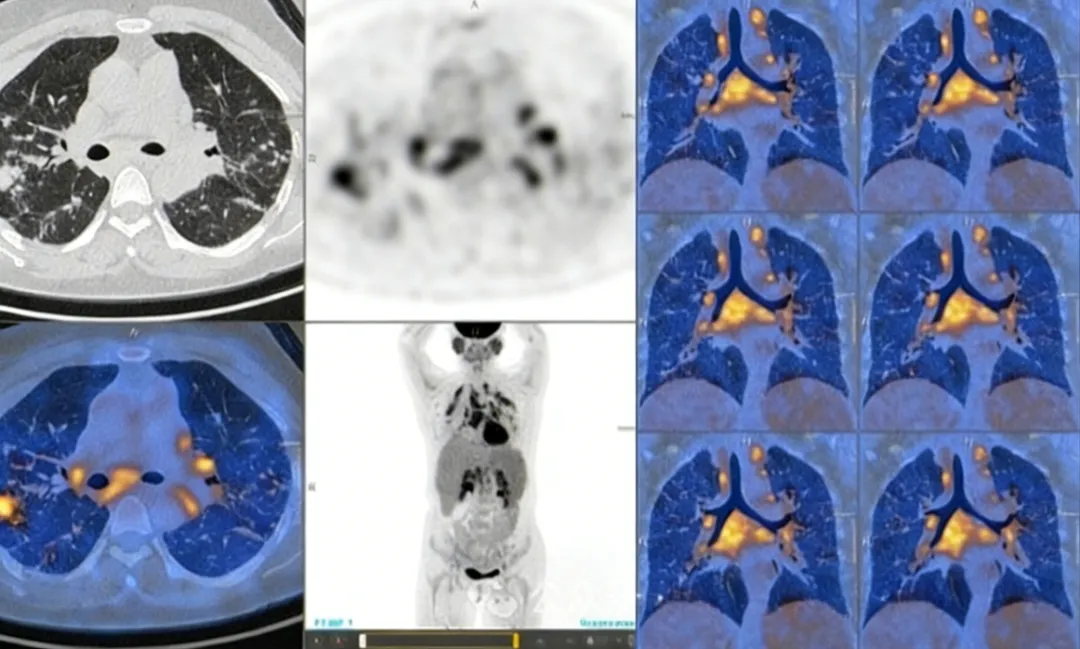

生理性摄取伪影

a.胃腔高代谢浓聚影;

b.口服造影剂充盈胃腔的延迟扫描显像。

(病例来源:陈蕾蕾,陈自谦,许尚文,肖慧,钟群,付丽媛,钱根年.PET/CT显像常见伪影及质量控制[J]中国医疗设备.2019.34(02):17-24.